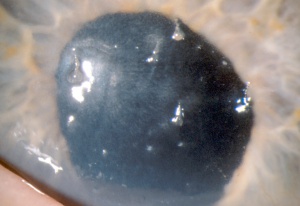

Slit lamp examination reveals filaments or mucoepithelioid strands adherent to the corneal surface that vary from 0.5 mm to 10 mm in length. A gray subepithelial opacity can sometimes be seen at the base of the filament. Blinking causes painful traction on the filaments and may detach them, leaving behind an epithelial defect. Filaments stain best with rose Bengal, but they can be seen with fluorescein as well. The location of the filaments can help determine the underlying cause: filaments due to dry eye syndromes tend to be found in the interpalpebral space, those due to ptosis are often located superiorly, and those due to surgery are found at the site of the wound or surgical trauma.

Signs include multiple filamentary attachments firmly adherent to the corneal surface, decreased aqueous tears, increased mucin in the precorneal tear film, subepithelial opacities at the base of filaments, or frank corneal epithelial defects.